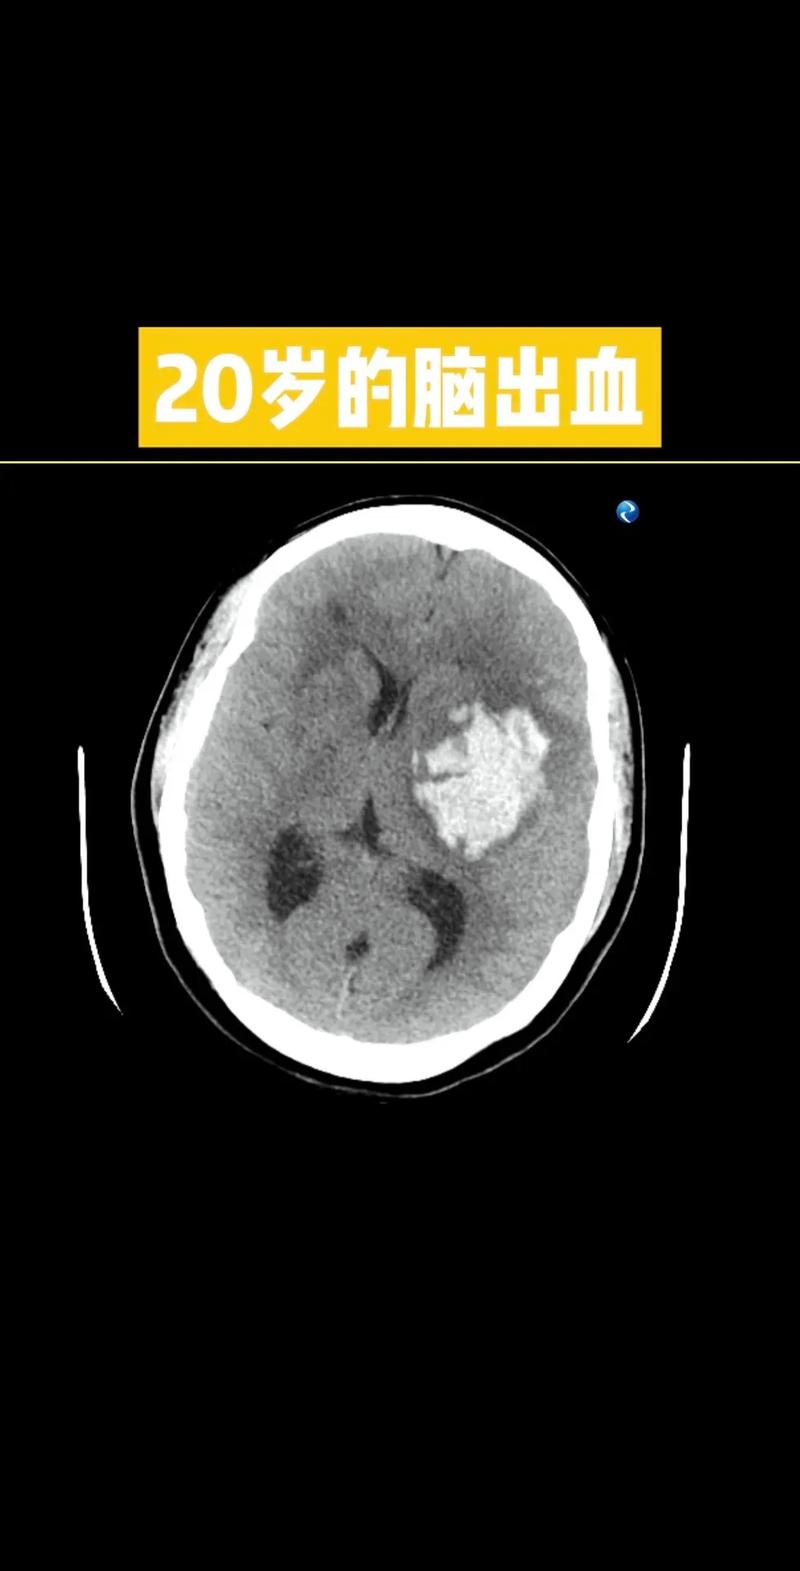

脑梗后脑子又有新出血

(图片来源网络,侵删)